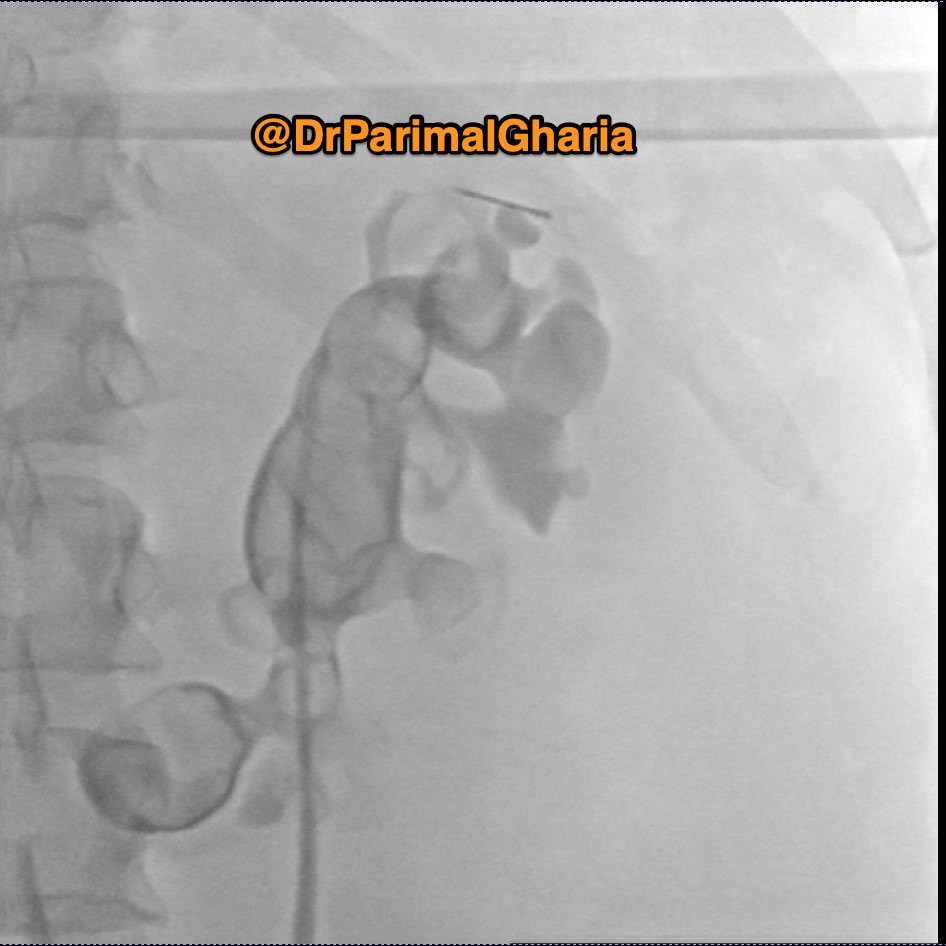

Bladder Mass or Cystitis? #Cystoscopy